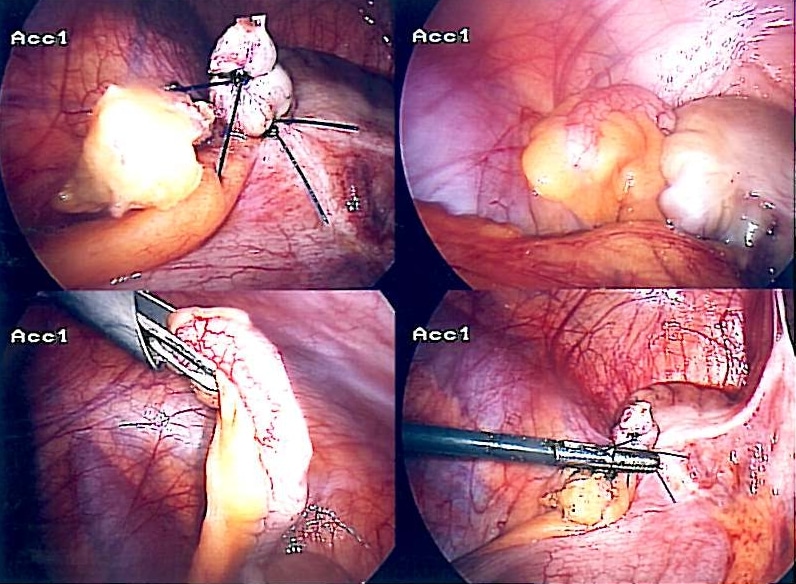

Images showing the removal of an inflamed appendix through a laparoscopic surgery

Images showing the removal of an inflamed appendix through a laparoscopic surgery